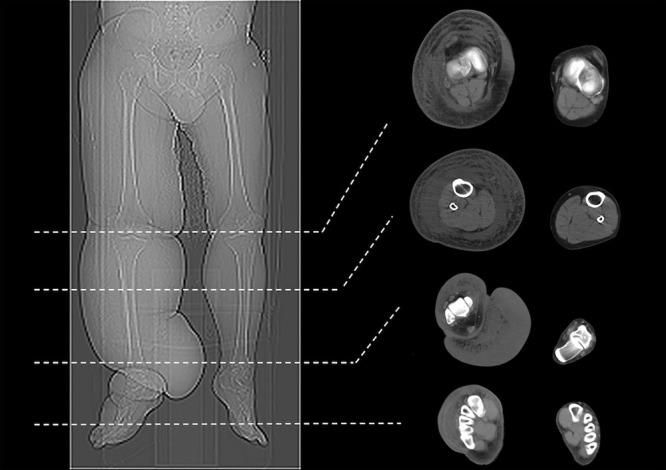

Circumferential difference of lymphedematous limbs at designated anatomic distances has been the primary mode for measuring lymphedematous extremities. Computed tomography (CT) imaging produces accurate, consistent, hygienic volume measurements and a direct limb representation. This study compares these 2 main modalities and assesses their correlation.

CT and circumferential difference measurements, costs, and correlation of patient limbs that received vascularized lymph node transfer were compared.

Mean circumferential difference by tape measurement pre- and postoperatively was 31.4% ± 19.1% and 17.4% ± 8.8% for upper limbs and 43.2% ± 16.1% and 22.4% ± 12% for the lower limbs, respectively. Mean CT volumetric difference pre- and postoperatively were 36.1 ± 4.1% and 27.2 ± 2.8% for the upper limb and 46.2 ± 3.2% and 33.2 ± 2.1% for the lower limbs, respectively. CT volume measurements significantly correlated with their respective circumferential difference with Pearson correlation coefficient of = +0.7, which was statistically significant ( = 0.03), indicating a strong positive correlation between circumferential difference and actual limb volume changes as determined by CT imaging. Circumferential differences are more cost effective than CT volume assessments in the domains of measurement frequency ( = 0.03), fee ( < 0.01), time ( = 0.03), total cost per year ( < 0.01), and cost/minute ( = 0.03).

Standardized circumferential differences that are currently used are comparable to unbiased CT volumetric measurements and can be used as a reliable, reproducible, minimally invasive, low cost, and accurate method of measuring the lymphedematous limbs.